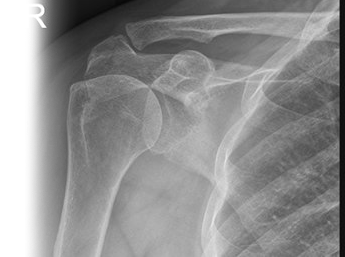

Рентгенография плечевого сустава – важный метод прицельного исследования, который позволяет оценить состояние плечевого сустава. Диагностическая услуга выполняется в двух проекциях.

Показания для проведения рентгена плечевого сустава:

• травма, боль, отек в области плечевого сустава.

Рентген позволяет исключить патологию плечевого сустава костно-травматического, дегенеративно-дистрофического, опухолевого генеза.